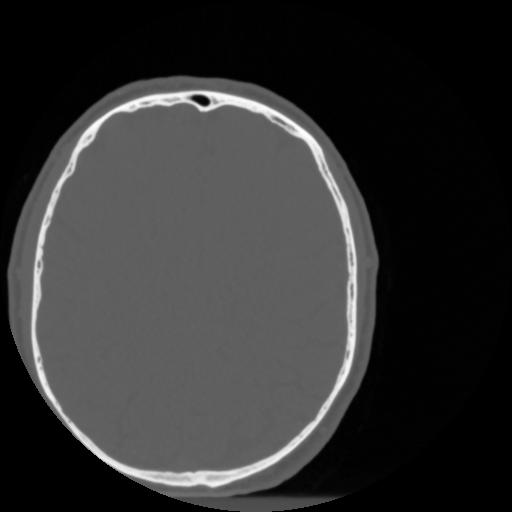

4 CEREBRO,,Vol,0.5,CEREBRO,,